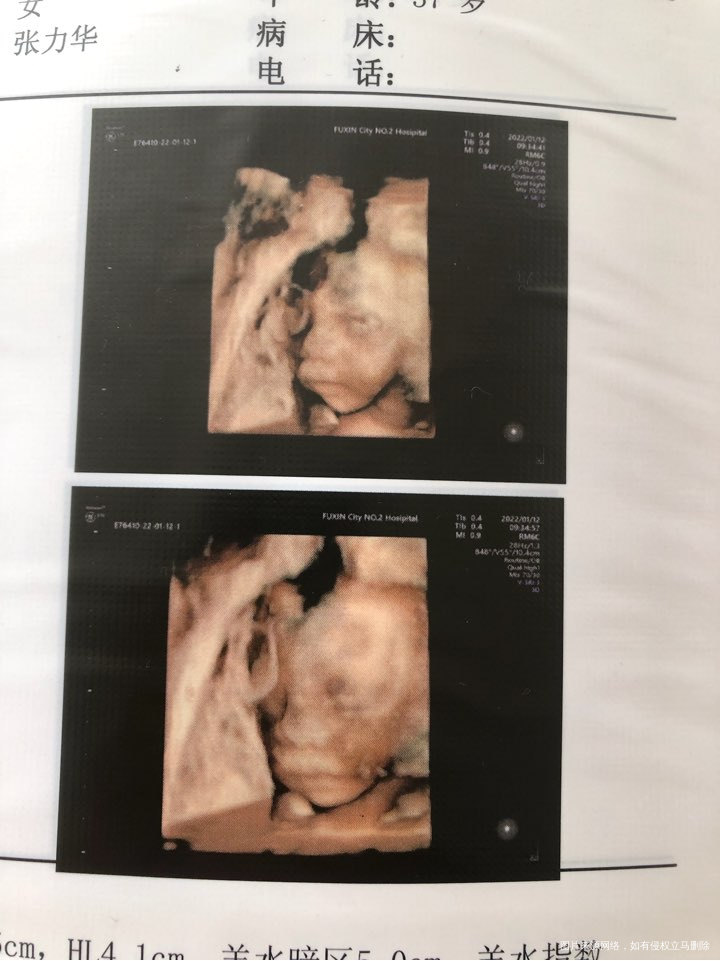

今天做四维一次性通过了。你真棒!不过医生说妈妈太胖了图像不清晰,不过也一次性过了,你真的太给力哈哈。显示你绕颈一周希望你自己别那么贪玩慢慢绕回来哦,比实际周数小一周,妈妈会努力吃有营养的东西,咱们一起加油